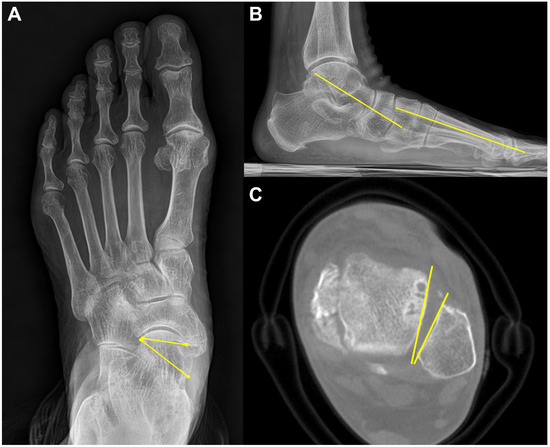

Lastly, Kim et al. suggested that talar malrotation in the axial plane should be considered an underlying feature of abduction deformity in PCFD [45]. They detected that the talus was significantly more internally rotated in reference to the lateral malleolus, the ankle transmalleolar axis, and the lateral malleolus in PCFD patients compared to controls (Figure 9). Moreover, the severe abduction group (talonavicular coverage angle (TNC) > 40 degrees) showed more internal rotation compared with the moderated abduction group (TNC 20 to 40 degrees). With the use of WBCT, surgeons can take axial components of PCFD into consideration at the time of reconstructive surgery in PCFD.

Figure 9.

A 71-year-old male PCFD patient with 35-degree talonavicular coverage angle (A) and 20-degree lateral Meary’s angle (B). The talus is internally rotated with regard to lateral malleolus on the weight-bearing CT axial image (C).